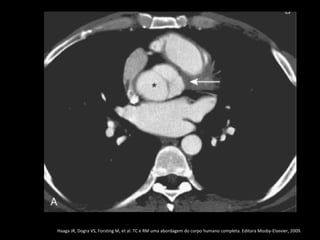

Dissecção aórtica

Stanford B

O flap intimal localiza-se após a emergência da

artéria subclávia esquerda;

É importante localizar os sítios de laceração porque

a cirurgia e os procedimentos de colocação de

prótese objetivam a oclusão das lacerações para

induzir a formação de trombo na luz falsa;

Multidetector CT of Aortic Dissection: A Pictorial Review 1. Radiographics march-april, 2010.